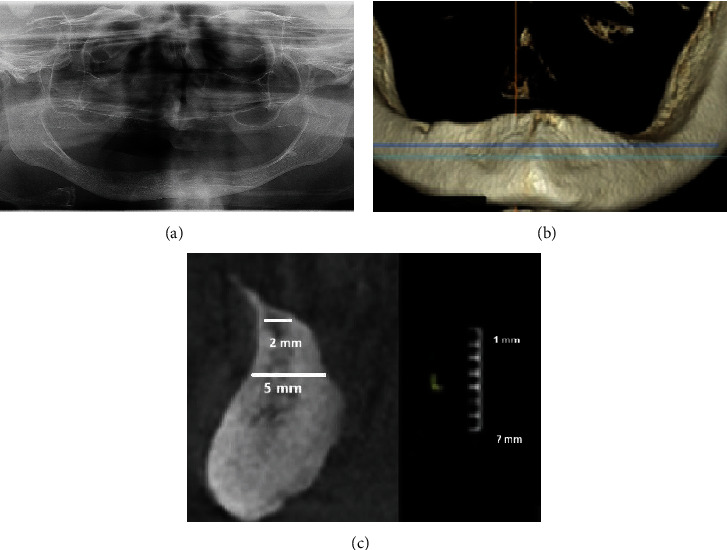

本临床报告描述了一名 78 岁的患者在无牙颌萎缩的下颌骨中植入微型种植体后,前庭活动粘膜直接接触微型种植体球头而引发眶下溃疡的情况,该患者已有 10 多年未佩戴传统下颌全口义齿。由于牙槽嵴严重萎缩,因此可以选择植入微型种植体(2.0 毫米宽),而无需进行广泛的外科手术。患者签署了知情同意书。种植体植入几天后,在与微型种植体相对的右侧前庭活动粘膜上发现了损伤、炎症和压痕。炎症的原因是口周肌肉张力增加,将活动粘膜推向微型种植体头,造成机械性创伤。在正畸期间,口周肌张力增加,将嘴唇和脸颊的粘膜推向残留的牙脊,使食物得以粉碎。由于患者没有旧的下颌义齿来覆盖微型种植体头,为了治疗持续性褥疮,在微型种植体头周围放置了大量牙科复合树脂,并进行了光固化处理,以保护粘膜免受进一步的机械性创伤。此外,还进行了前庭成形术(拔除活动附着物并加深前庭)。手术后,制作了一个类似于咬合缘的硅胶夹板,以保护粘膜,使加快脱落的药物就位,减少新假牙戴入前的口周肌肉张力,并防止活动组织复发。定制印模、颌骨关系确定和人工牙试戴都是在缝合线仍在原位的情况下进行的。安装假牙和植入种植体后,医生嘱咐患者戴着假牙睡觉,以保护活动粘膜。一年后,几乎没有观察到种植体周围边缘骨质流失,附着粘膜和种植体周围粘膜健康,患者非常满意。

This clinical report describes how a decubital ulcer arose from the direct contact of the vestibular movable mucous membrane against mini-implant balled-type heads after the mini-implant insertion in the edentulous atrophic mandible of a 78-year-old patient who was not wearing a conventional mandibular complete denture for more than 10 years. Due to severe alveolar ridge atrophy, mini-implant insertion (2.0 mm wide) was an option without extensive surgical procedures. The patient signed the informed consent. A few days after the implant insertion, injury, inflammation, and induration of the vestibular movable mucous membrane were observed on the movable vestibular mucosa on the right side, opposing the mini-implants. The cause of inflammation was attributed to increased perioral muscle tonus which pushed the movable mucosa onto the mini-implant heads and caused mechanical trauma. During the period of edentulism, the perioral muscle tonus increased, directing the mucous membrane of the lips and cheeks against residual ridge to enable food comminution. To treat the persistent decubitus, a bulk of dental composite resin was placed around mini-implant heads and light-cured to protect the mucosa from further mechanical trauma, as the patient did not possess an old mandibular denture to cover the mini-implant heads. Vestibuloplastic surgery (disinsertion of movable attachments and deepening of the vestibulum) was also done. After the surgery, a silicone splint, resembling an occlusal rim, was made to protect the mucous membrane, keep medicaments for faster epitalization in place, to decrease perioral muscle tonus before the new dentures' delivery, and to prevent movable tissue relapse. The custom impression, jaw relationship determination, and try-in of the artificial teeth setup were made with sutures still in place. After the denture delivery and implant loading, the patient was instructed to sleep with the dentures to protect the movable mucous membrane. One year later, almost no peri-implant marginal bone loss was observed, attached and peri-implant mucosa were healthy, and the patient was delighted.